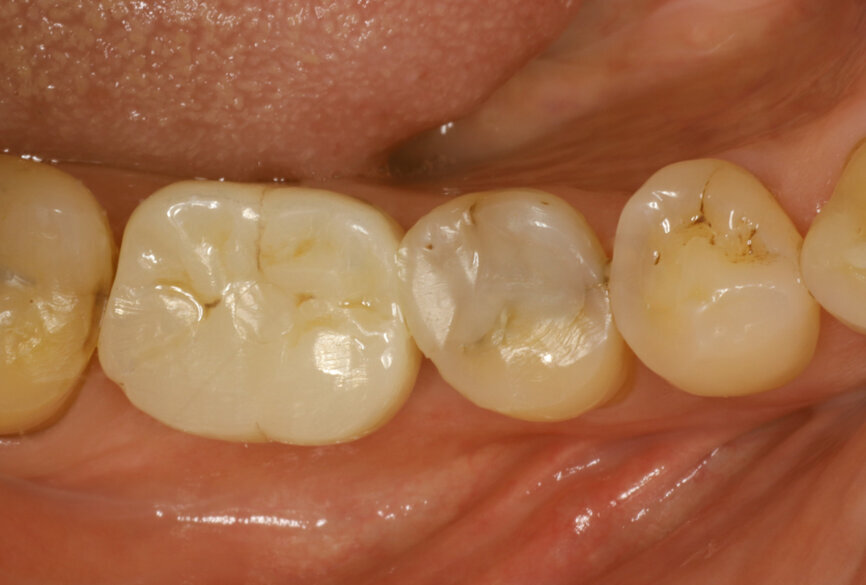

Fig. 1: Intra-oral occlusal view.

After careful assessment of the patient’s anatomical condition through a panoramic radiograph and CBCT scan (Figs. 1–3), it was possible to verify ideal interradicular bone availability, allowing the following treatment plan:

A 68-year-old male patient, a non-smoker, presented with controlled Type 2 diabetes. He had undergone previous dental implant treatments with positive results in the past. The patient presented to the office with tooth #36 in a non-restorable condition with indication for extraction. He requested a dental implant as the treatment choice.